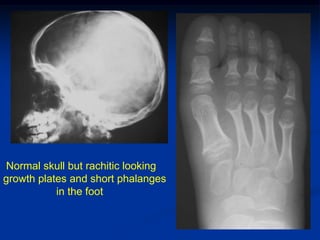

Case #1     Jansen’s Type Metaphyseal Dysplasia

Young boy with short limbs with wide growth plates like rickets

Normal skull but rachitic looking

growth plates and short phalanges

in the foot